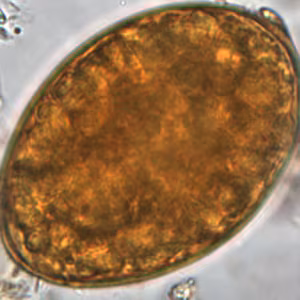

Diphyllobothriid eggs

Diphyllobothriid eggs are oval or ellipsoidal and range in size from 55 to 75 µm by 40 to 50 µm. There is an operculum at one end that can be inconspicuous, and at the opposite (abopercular) end is a small knob that can be barely discernible. The eggs are passed in the stool unembryonated. Although eggs of Adenocephalus pacificus are generally smaller than those of Dibothriocephalus spp. and Diphyllobothrium spp., there is a degree of overlap and thus species identification based on eggs may not be reliable.

Microscopic identification of eggs in the stool is the basis of family level diagnosis; genus level identification based on eggs is difficult due to overlap in morphological features. Eggs are usually numerous and can be demonstrated without concentration techniques. Identification of proglottids passed in the stool is also of diagnostic value.